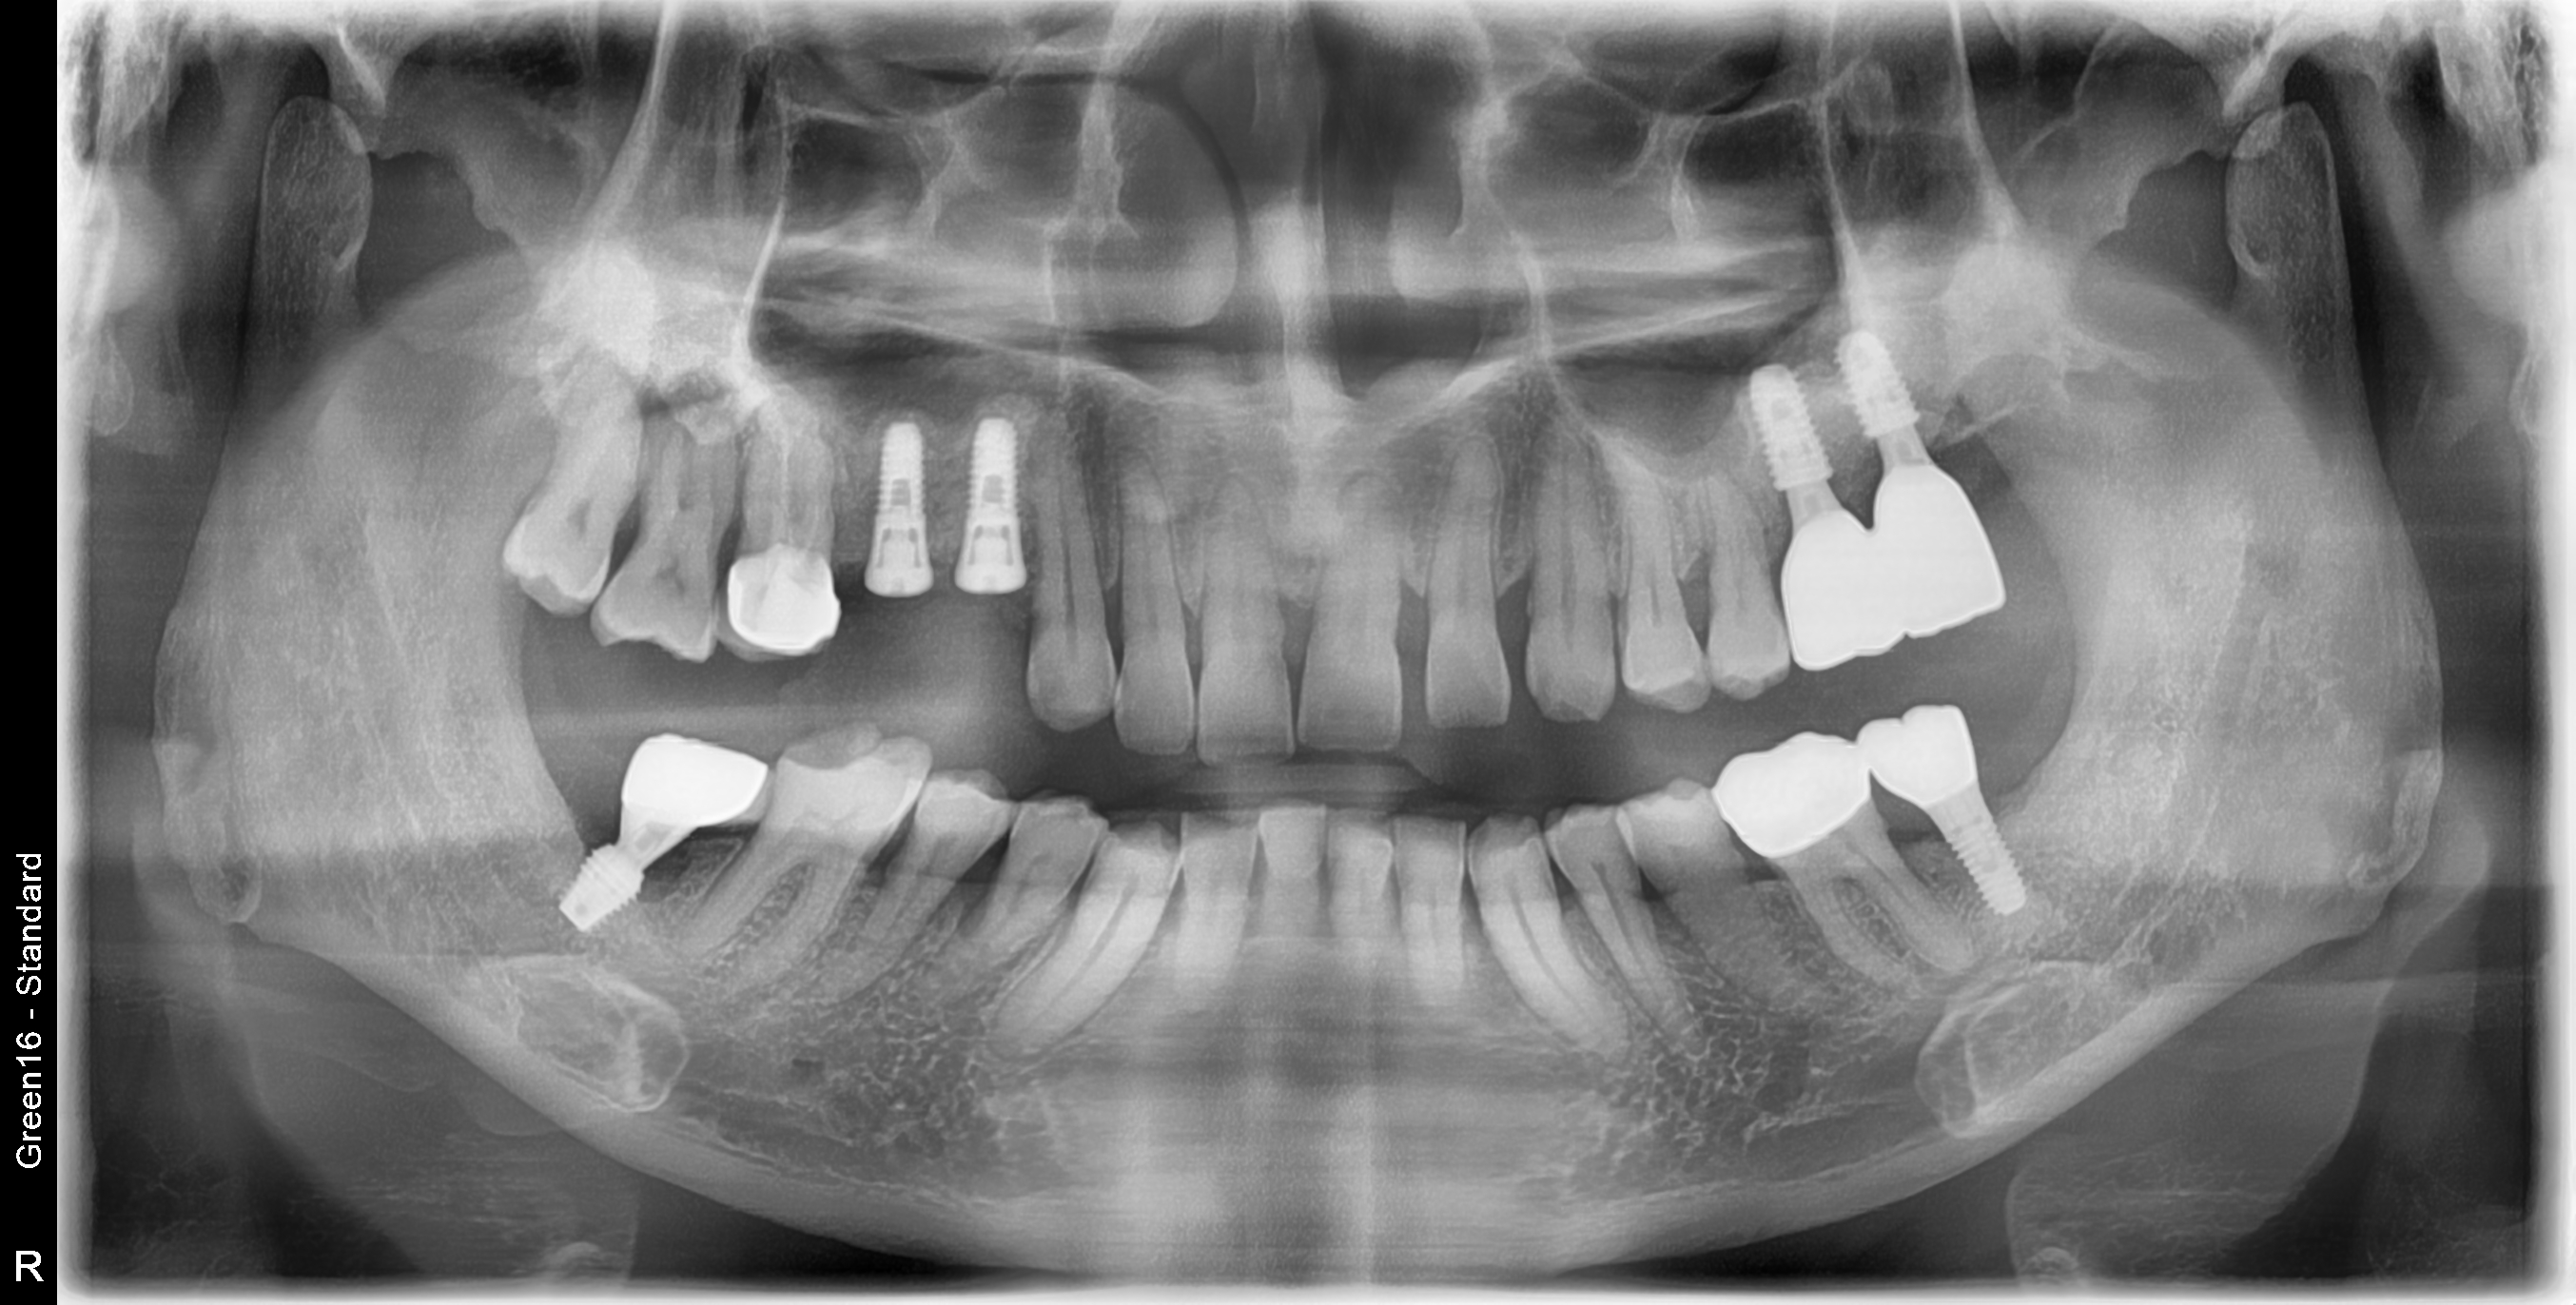

This is a male patient in his mid-50s.

A window approach was performed in the left maxillary sinus, but the patient was referred due to symptoms of infection, including the presence of pus in the surgical site.

Irrigation of the left maxillary sinus was performed through the oral cavity by inserting a drain as shown in the image.

This is an intraoral photo. After careful consideration, implant placement was performed using the remaining bone with the additional procedures of crestal approach and bone grafting.